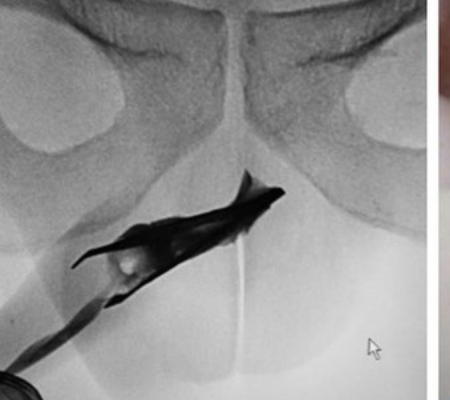

Médicos participaram de uma delicada operação para remover uma pinça do interior do pênis de um homem de 22 anos. O paciente, que não teve a identidade divulgada, relatou que não sofreu nenhuma dor desde que inseriu o objeto na uretra há quatro anos. As informações são do IG.

Durante a operação, os profissionais precisam aplicar pressão em ambos os lados do pênis para manter a pinça de quase sete centímetros fechada. Isso porque, caso a remoção do item acontecesse enquanto estivesse aberto, as pontas afiadas poderiam danificar a uretra.

O raio-X mostrou que a pinça tinha se encaixado no topo da uretra esponjosa. A retirada do objetivo foi feita enquanto o paciente estava sob anestesia geral. “Ele foi para casa após o procedimento. Ele se recusou a passar por uma avaliação psiquiátrica”, dizem os médicos.